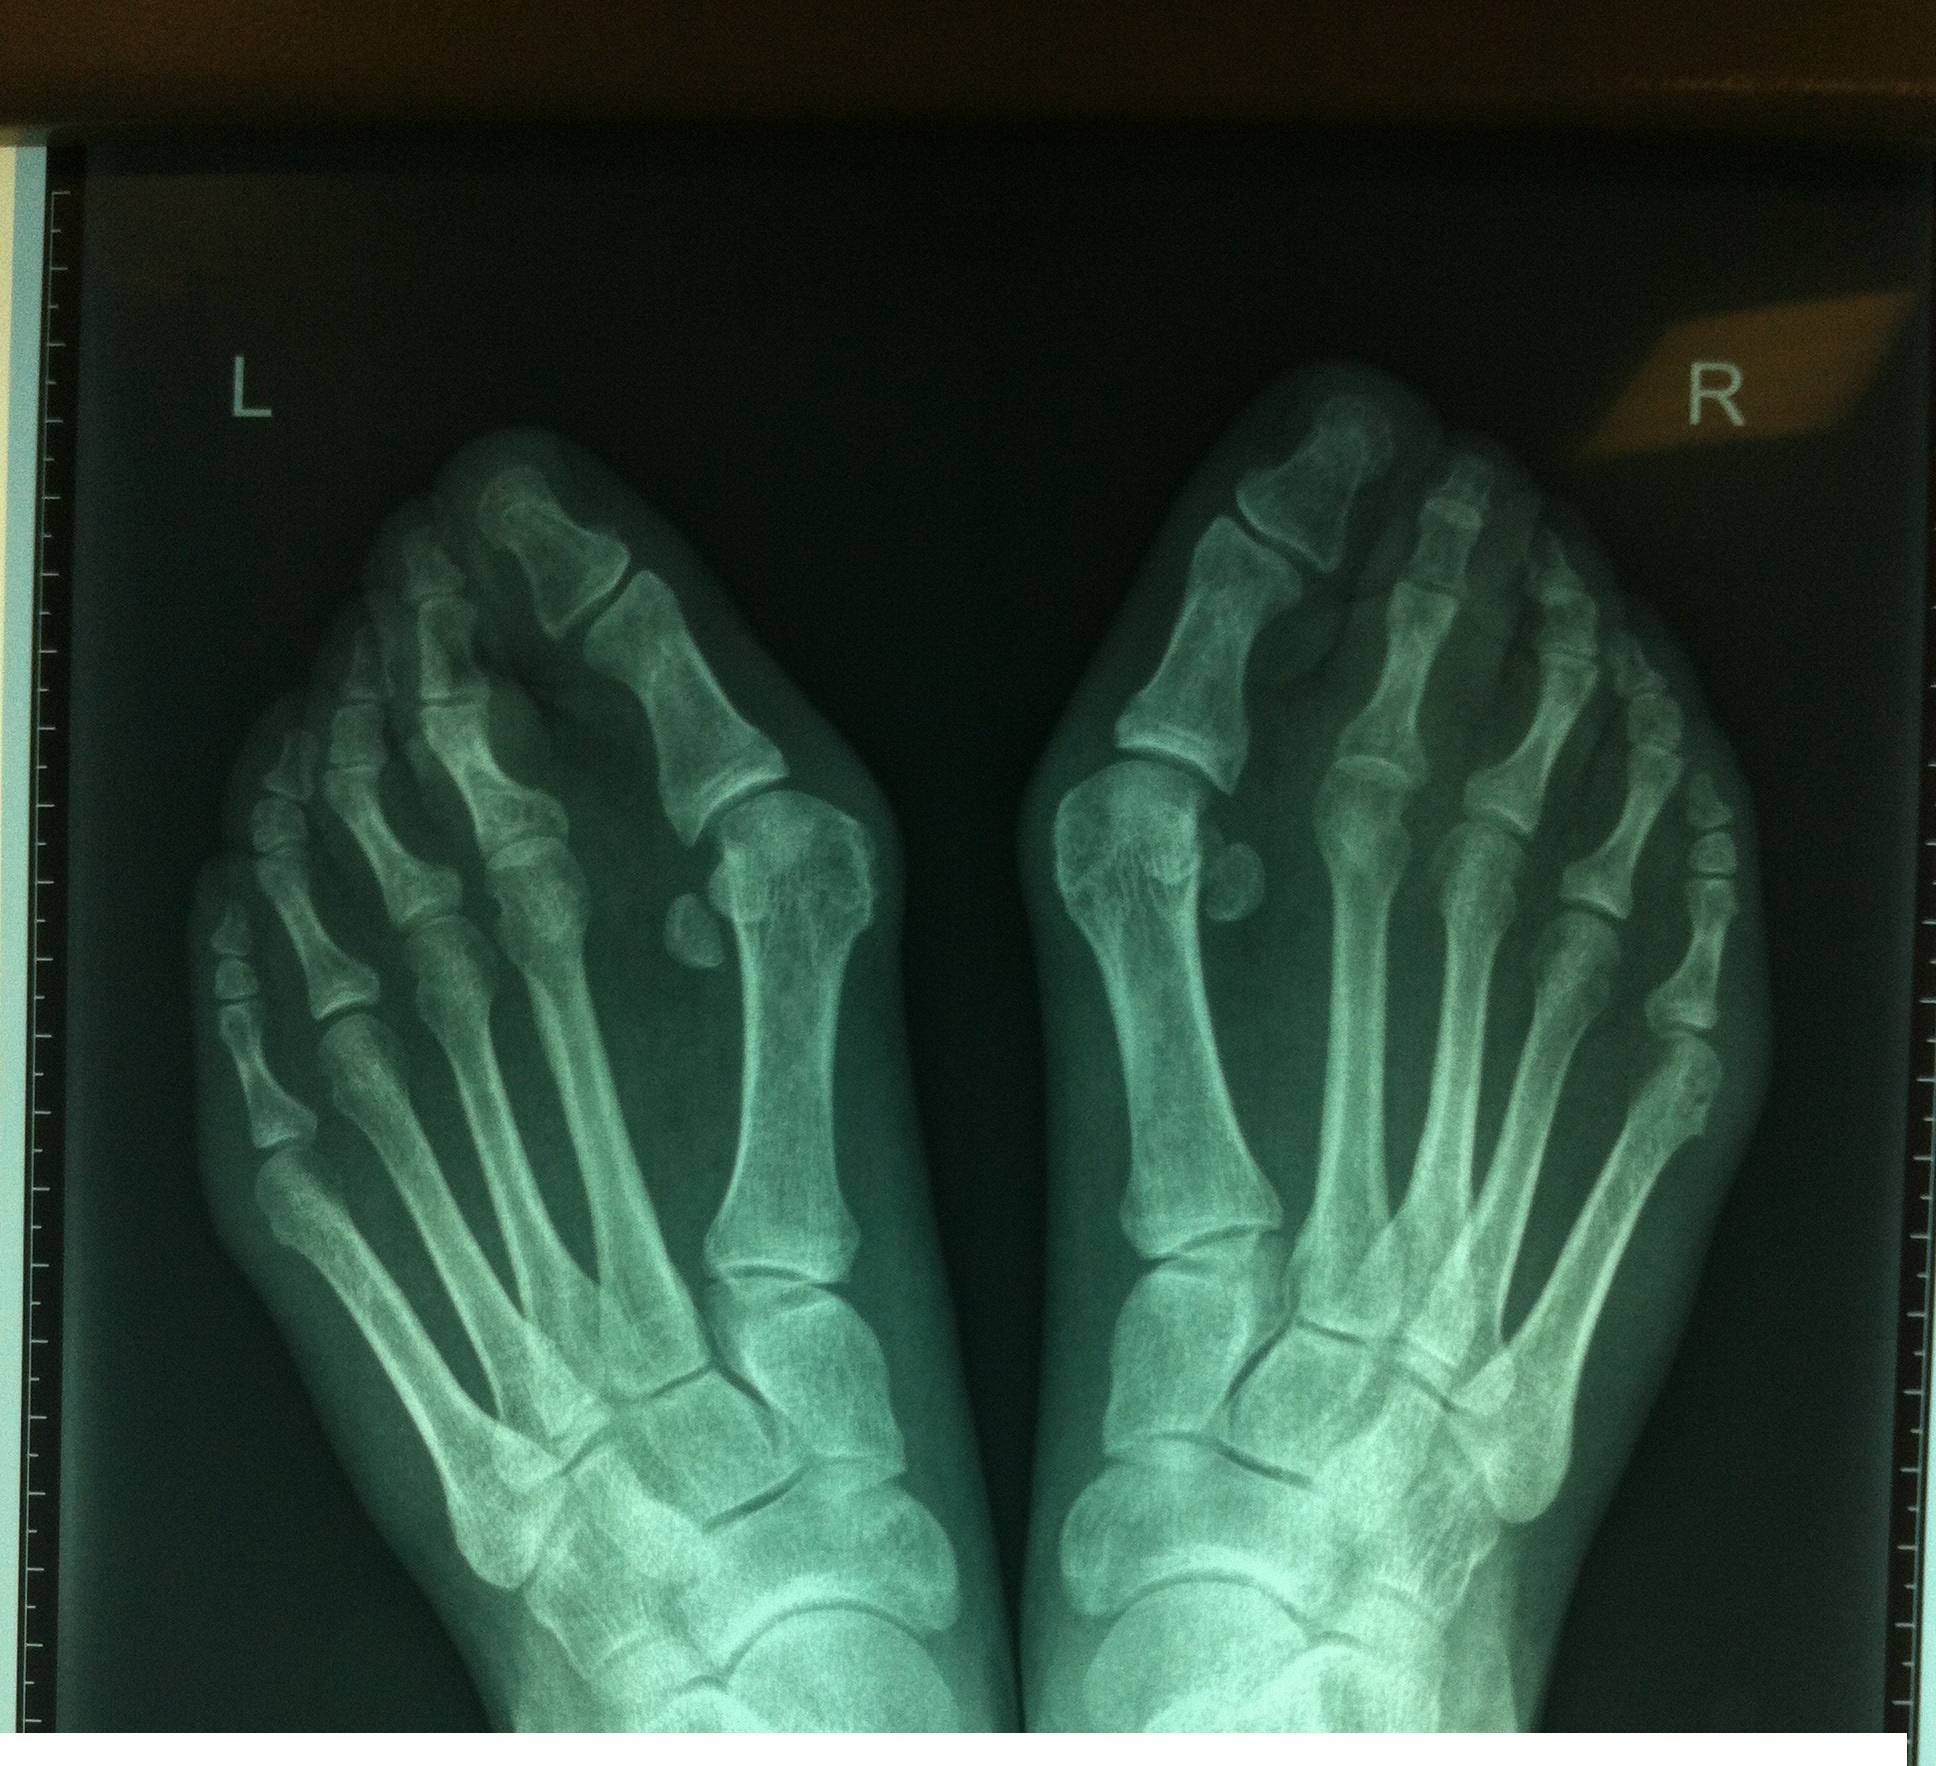

Вальгусная деформация первого пальца стоп (автор: врач травматолог-ортопед Кривокрисенко Владимир Юрьевич)

В современном мире вальгусная деформация первого пальца стоп очень актуальная проблема в виду того, что часто общество или работа ограничивает в выборе обуви. Вальгусная деформация первого пальца формируется на фоне поперечного плоскостопия, которое, в свою очередь, в той или иной мере есть у всех людей. Однако, когда на фоне поперечного плоскостопия на стопу влияют такие факторы как: модельная обувь; длительная ходьба или просто положение стоя; повышенная эластичность связочного аппарата или состояния организма, повышающие его эластичность.

Возвращаясь к вопросу о вальгусной деформации, нужно отметить, что кроме эстетического момента и трудности в подборе обуви на первый план выходит неправильное положение стопы при ходьбе, что в свою очередь, нарушает, главным образом, амортизационную функцию стопы, что изнашивает суставы стоп, коленные суставы, перегружает поясницу и мышцы голеней, а это — дополнительные факторы в формировании остеохондроза и варикозной болезни вен нижних конечностей.

При более поздних проявлениях поперечного плоскостопия, когда к выраженной деформации первого пальца присоединяется молоткообразная деформация малых пальцев или сочетание с подвывихом пальцев, к сожалению, без оперативного лечения не обойтись. Современные методы хирургического лечения отличаются малотравматичностью, эффективностью, крайне низким риском рецидивов и довольно короткими сроками нетрудоспособности. Современное силовое оборудование позволяет поменять конфигурацию костей, снижая вероятность рецидива до минимума. Применяемые при операции импланты из титана не нужно удалять, нет ограничений по выполнению МРТ-исследований, так же они не обнаруживаются металлодетекторами, что позволяет избежать лишнего внимания при перелетах и определенных мероприятиях.